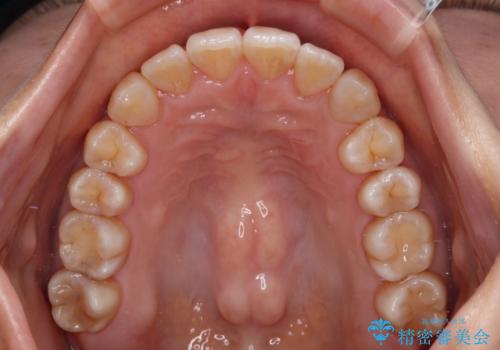

クロスバイトの前歯を改善 ワイヤー装置で楽々矯正治療

舌のトレーニングをしっかりと行っていただき、補綴治療も含めて1年強の短期間で治療を終えることができました。